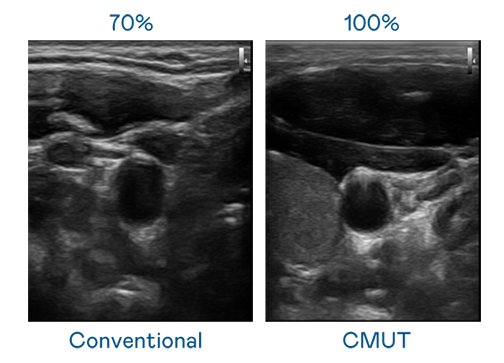

CMUT 技术是一种用电容式微机电元件来产生超音波讯号的技术。与传统 PZT 压电式技术相比,CMUT 频宽增加 30%,更宽频的超音波讯号让影像解析度大幅提升,是实现高影像品质医疗超音波扫描、促进精准医疗发展的关键技术。

超音波影像的解析度高低,首先取决于探头能发出的讯号频宽。JJB竞技宝 CMUT 可提供高清晰的超音波讯号,提供高频宽、高灵敏度、影像纹理细节更高的超音波影像,协助医护人员缩短影像判读时间及利用精准的医疗影像进行诊断。